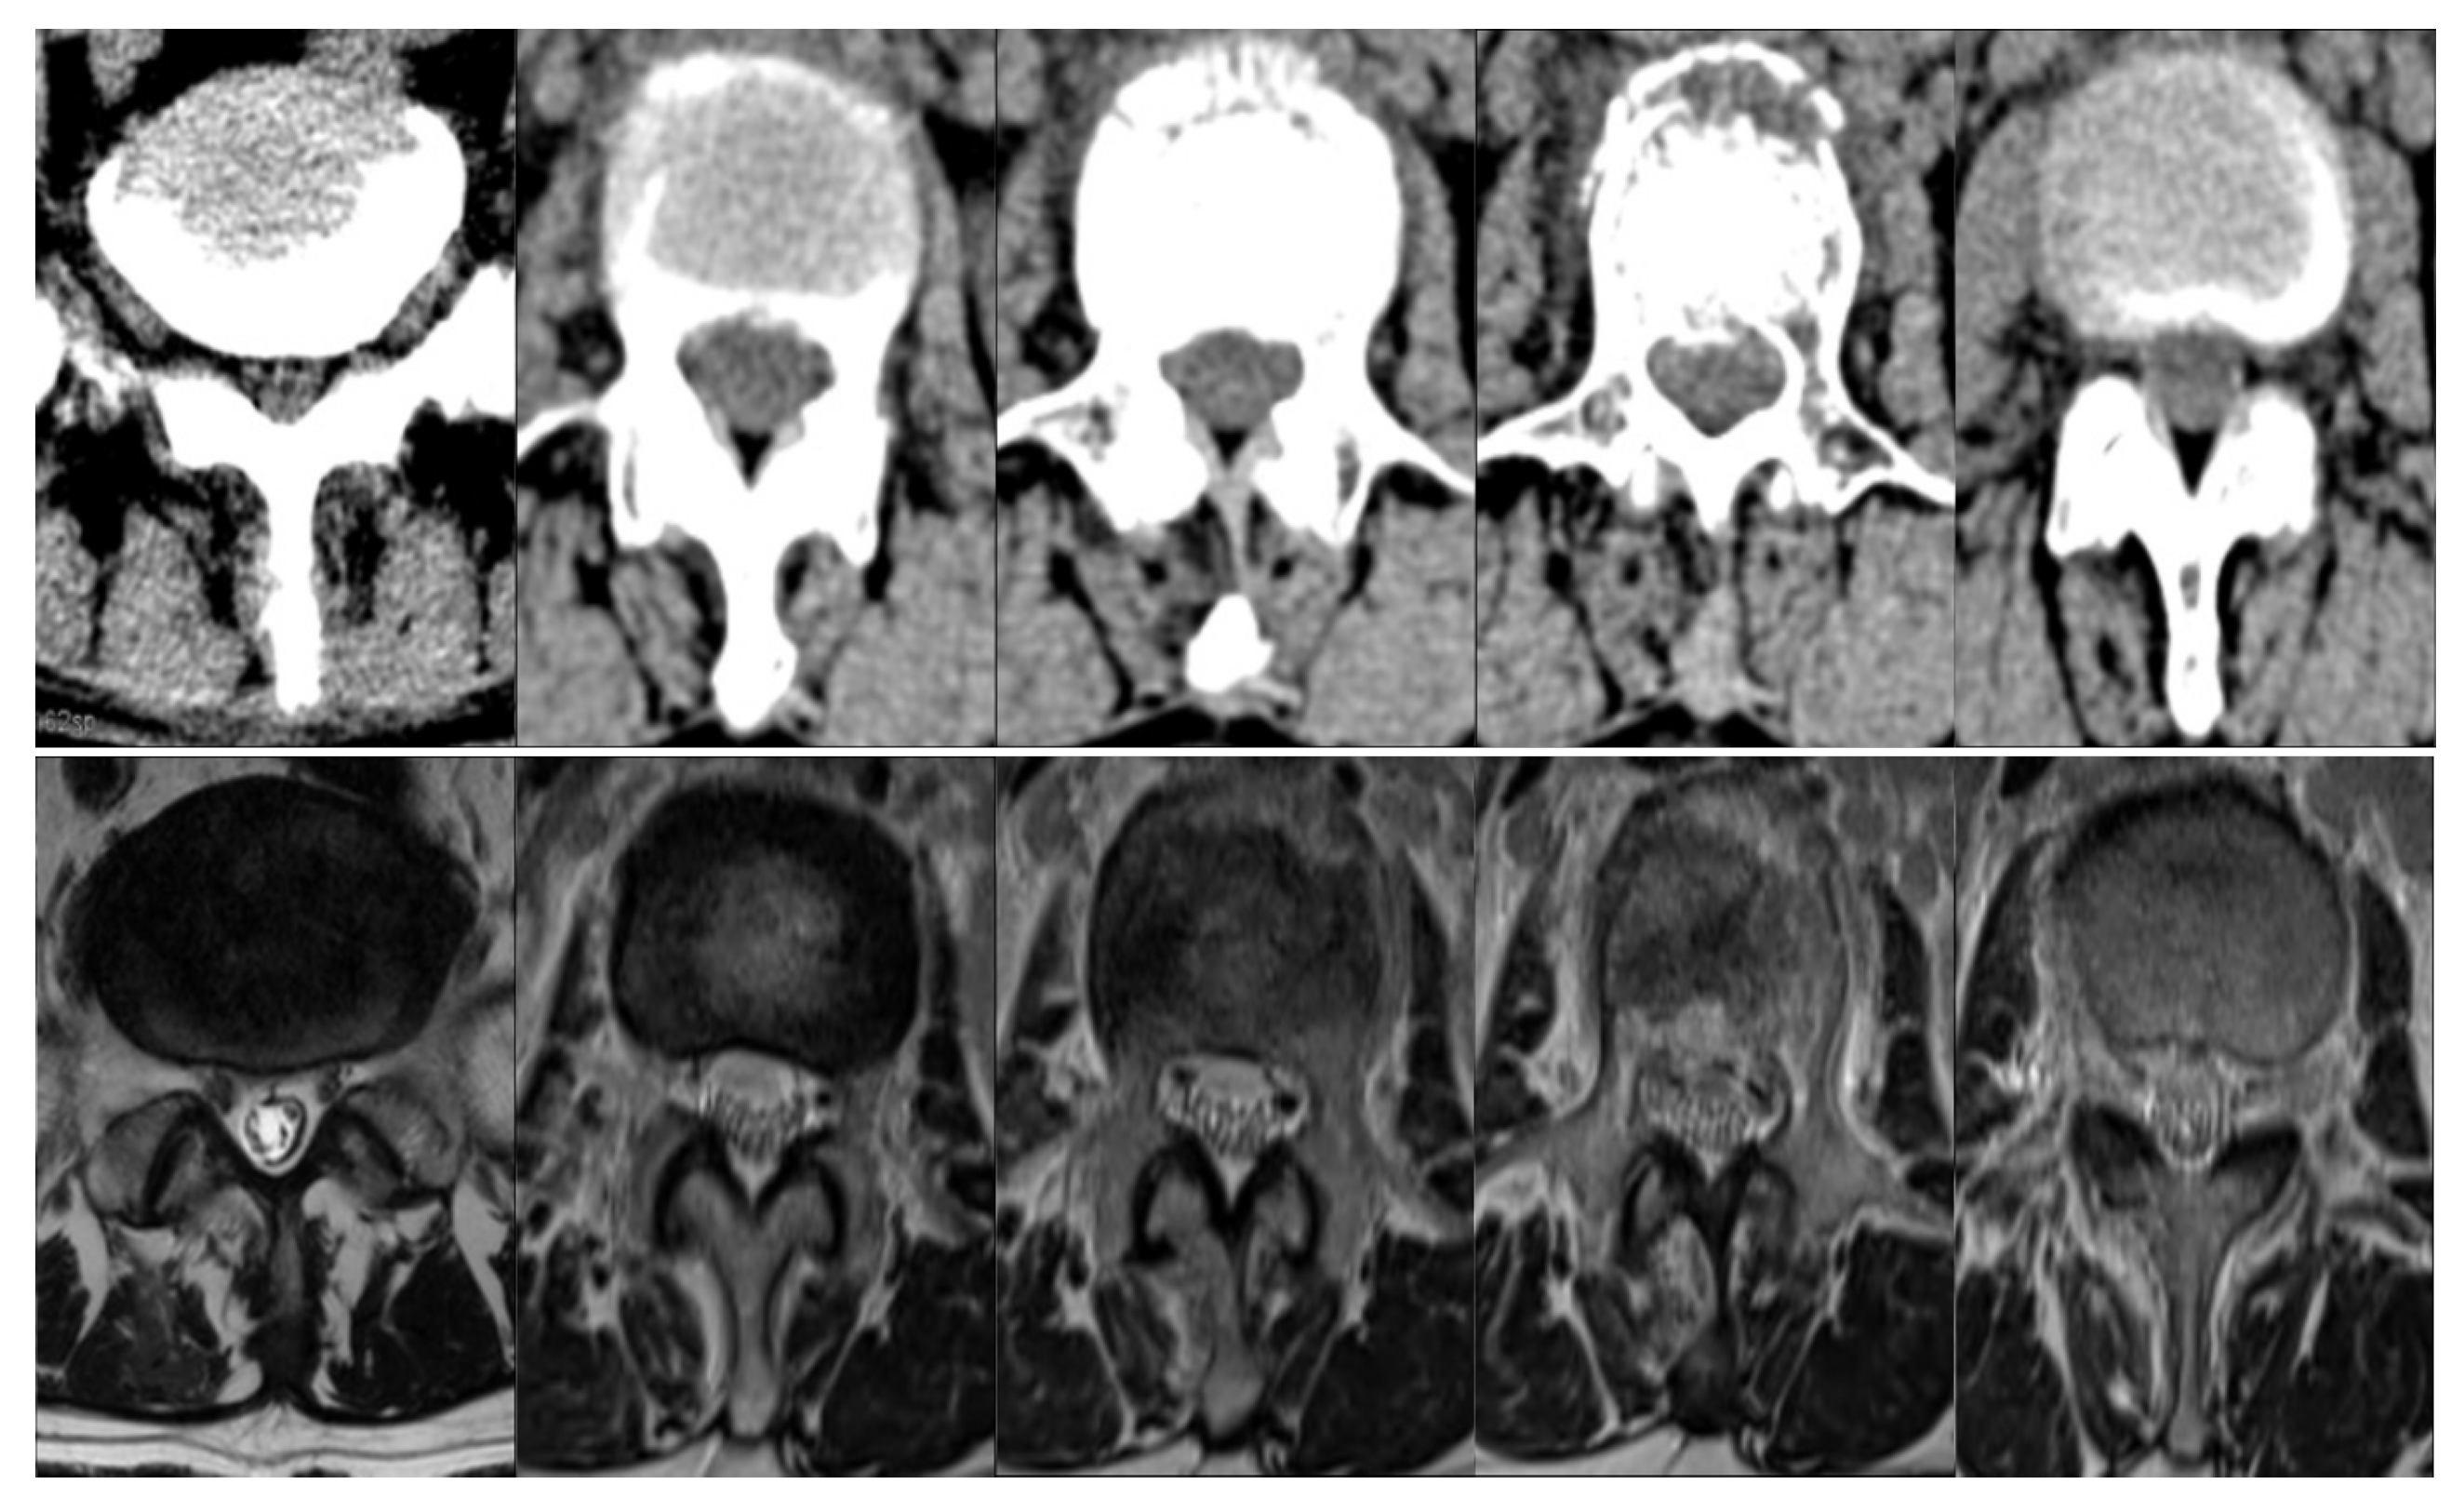

- The dual cycle-consistent adversarial network (DCAnet) is proposed as a general synthesis system for semi-supervised learning. Due to its dual cycle-consistent structure, DCAnet can be applied to both supervised and unsupervised learning.

- Jin, C.B.; Kim, H.; Liu, M.; Jung, W.; Joo, S.; Park, E.; Ahn, Y.S.; Han, I.H.; Lee, J.I.; Cui, X. Deep CT to MR synthesis using paired and unpaired data. Sensors 2019, 19, 2361. [Google Scholar] [CrossRef] [PubMed]